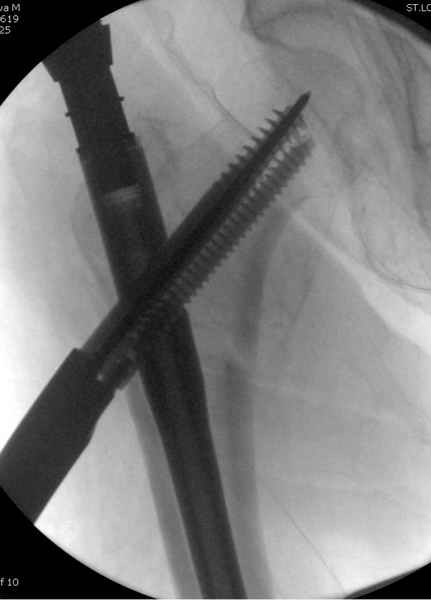

Мы получили испытательный вариант инструментария для пробы, хотя компания объявила, но ещё не для широкой публики, обещают к сентябрю. За полтора месяца, включая сегодняшнюю, вот уже восьмая операция по счету. Удобный инструментарий, ничего лишнего, научились делать быстро, посмотрим что будет, пока нравится.

Здесь сканнированные снимки импланта и операционные снимки больной.

На этом снимке процесс компрессии нижним болтом.

Итог